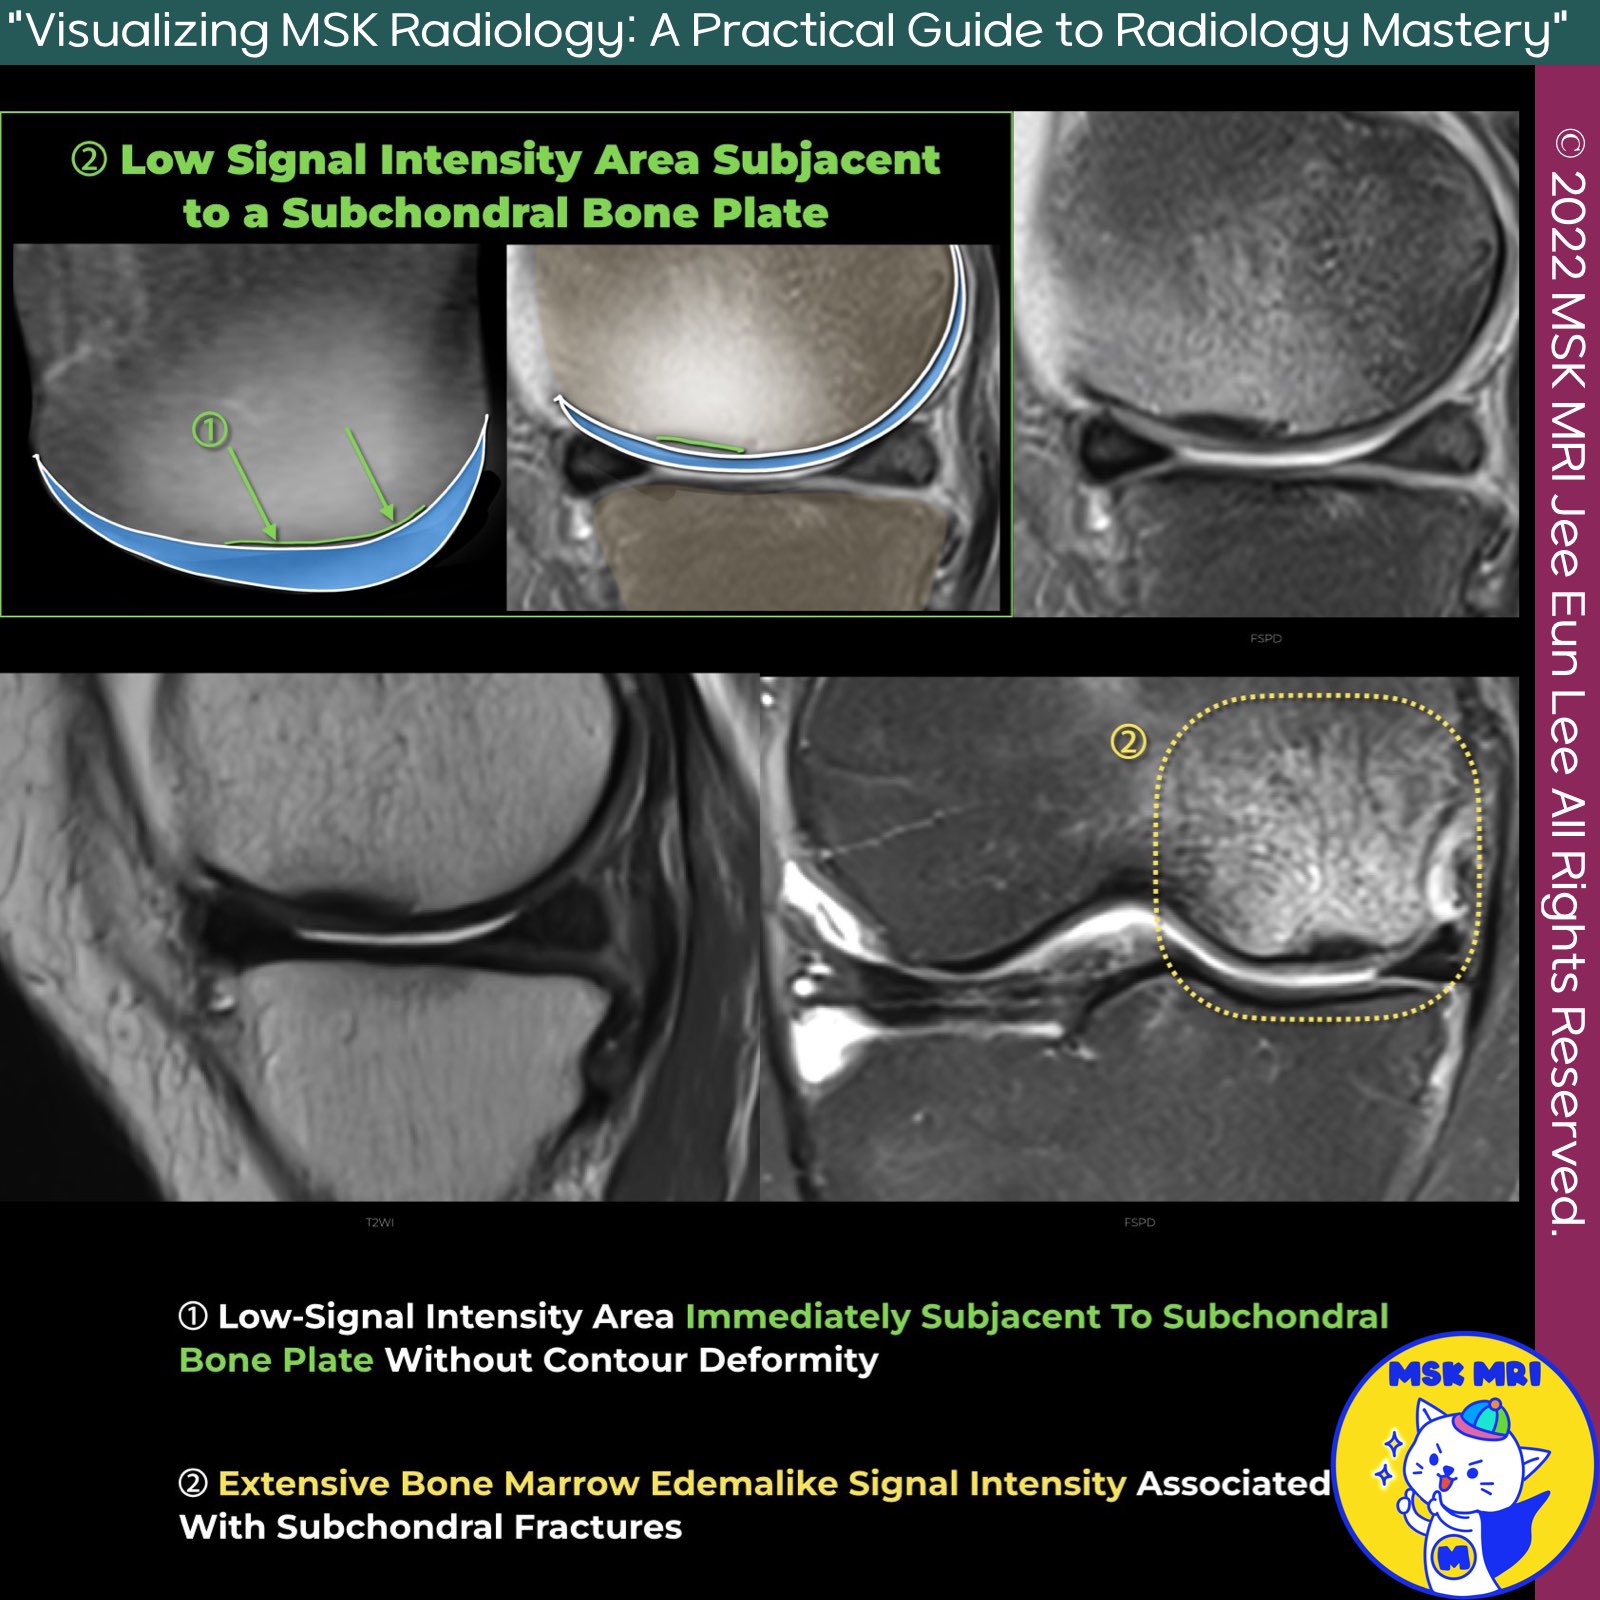

✅ Low Signal Intensity Area Subjacent to a Subchondral Bone Plate without Epiphyseal Collapse

1. Low-Signal Intensity Area Subjacent to Subchondral Bone Plate Without Contour Deformity

- Description: This finding appears as a low signal intensity fracture line running very close to the subchondral bone plate, giving the appearance of a thickened subchondral bone plate.

- Reason: This occurs due to a combination of a fracture with callus and granulation tissue and secondary osteonecrosis between the fracture line and the articular surface.

2. Extensive Bone Marrow Edemalike Signal Intensity Associated with Subchondral Fractures

- Description: This finding presents extensive bone marrow edema-like signal intensity related to subchondral fractures.

- Radiologists should note that the subchondral area of low signal intensity often integrates with the subchondral plate and should not be mistaken for a thickened subchondral plate.

- A dedicated MRI with a small Field of View (FOV) is recommended to evaluate individual morphologic findings in SIF, such as fracture lines, subchondral hypointense areas, subtle contour changes, cartilage loss, and the presence of collapse.